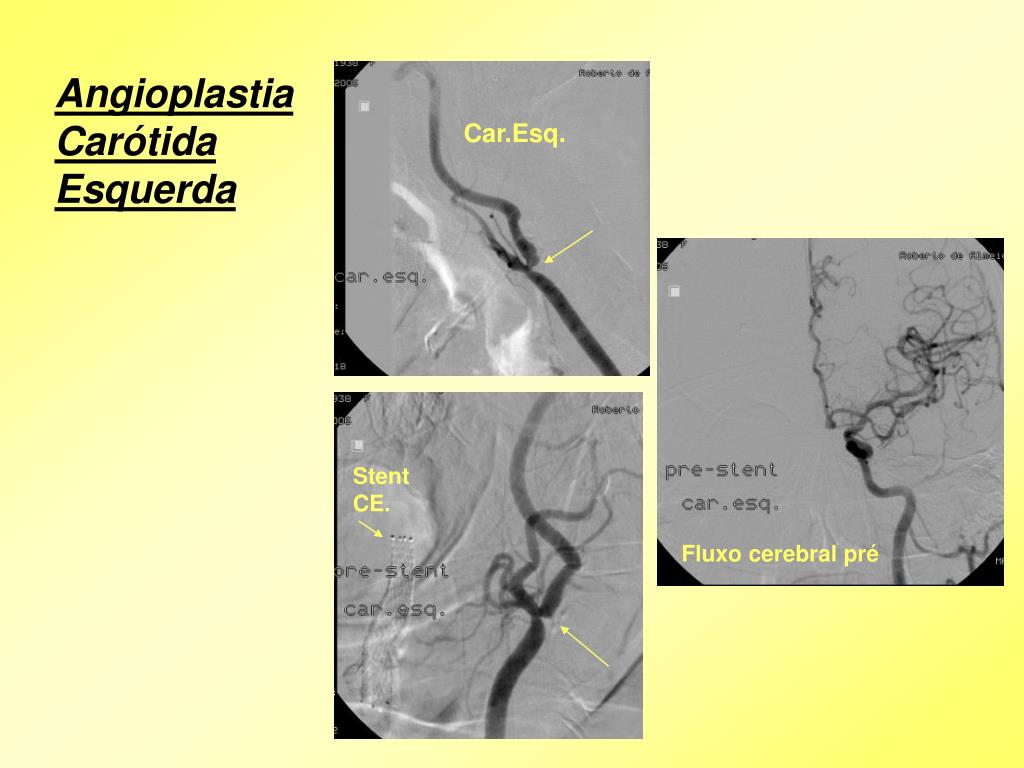

4. Angioplastia Carótida Esquerda Car.Esq. Stent CE. Fluxo cerebral pré